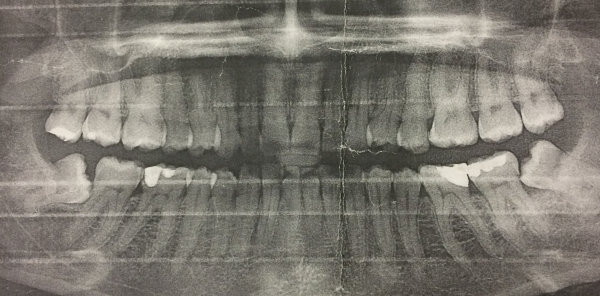

Добрый день! Моей дочери 16 лет. Лечимся несколько лет у ортопеда, исправляем прикус. Сделали контрольную ортоптограмму и доктор сказала, что нужно удалять восьмерки нижние, хотя они еще и не прорезались. Скажите в нашем случае это обязательно, или хотя бы можно подождать пока они наружу вылезут? И насколько это тяжелая процедура?

Да, скорее всего это обязательно, и процедура не из легких. Но я вам рекомендую не тянуть. Данные зубы в вашем случае являются причиной скученности зубов.

Я вам рекомендую записаться к нам на прием, и обязательно к дипломированному хирургу. Данное удаление считается очень сложным и проводить должен обязательно челюстно-лицевой хирург, чтобы избежать проблем впоследствии.